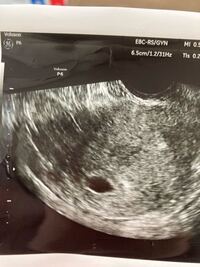

妊娠判定から卒業までの流れ 受精卵を移植された方は、妊娠判定を行い移植後の経過を見ていきます。 ①採血によるホルモン測定 (妊娠反応陽性) ②エコーによる胎嚢確認 (臨床妊娠成立) ③エコーによる胎児心拍の確認 (心拍確認) *妊娠週数について 妊娠 今日で生理予定日から一日経過中です。 排卵日から数えて今日で15日目です。 排卵日は検査済みなので間違いないと思います。 明日病院に行って胎嚢が確認される確率はありますか? 仕事の休みの関 心拍確認を迎えるためにも、まずは胎嚢確認を無事迎えるようにしてください。 関連記事 胎嚢の確認はいつから?流産の確率と心掛けたい過ごし方まとめ 胎嚢確認まで気をつけることは冷えと姿勢。

心拍確認 胎嚢が確認出来たら、つぎは赤ちゃんの 心拍確認 です。 心拍は妊娠6週~妊娠7週ごろ確認できることが多い ようです。 私は医師から(胎嚢確認の)2週間後に再診するように言われました。 妊娠7週3日の診察で、ドクドクととても早い赤ちゃん 妊娠をハッキリ確認できるのは、6週以降がいいと思います。 私も5週で行ったことがありますが、胎嚢は確認できませんでした。 あまり早いと、来週もまたっていわれますし、 自費診療になるので、1度に5000円弱かかりますから、 心拍確認できるのはいつから? 妊娠5〜6週(生理予定日より2週間以上すぎたあたり) になると、ほとんどの場合で赤ちゃんの心拍が確認できます。 この時期は妊娠2ヶ月あたり「妊娠初期」になります。 赤ちゃんの心拍は、基本的に「超音波検査」で